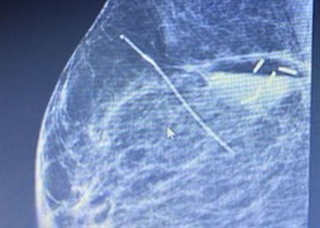

After a biopsy or tumor removal, the Accusyte fiducial sutures are sewn around the perimeter of the tumor bed at the anterior, posterior, middle, and lateral planes of the tumor cavity. The fiducials allow for accurate delineation of target volumes during treatment planning and assist with image guided radiation therapy (IGRT) before each session.

The fiducial markers are woven within an absorbable suture. When the body absorbs the suture, the fiducial markers remain within the tissue. Migration of the markers from their original position is unlikely, as the tissue produced during the healing process holds the markers in place. Sutures are sewn into place using the same technique as other sutures commonly used.

Disease site recommendations: Head & Neck, Breast, Lung, Abdomen, & Prostate.